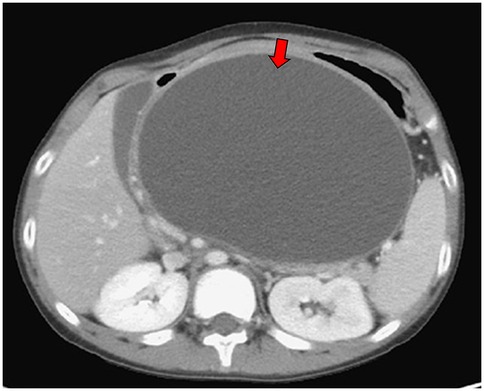

A 14-year and 6-month-old boy with a history of recurrent pancreatitis, ASD (with communication impairment), and learning disorder presented with frequent non-bilious vomiting for 1 day. Associated symptoms included epigastric fullness, nausea, left-lower quadrant abdominal pain, reduced activity, and decreased oral intake. His mother also reported a progressively enlarging epigastric mass. There was no fever, history of glucose-6-phosphate dehydrogenase deficiency, asthma, allergic rhinitis, or family history of autoimmune disease. On examination, the abdomen was protuberant with an ovoid, non-tender, mass-like lesion measuring approximately 10 cm × 10 cm, without rebound pain. Laboratory findings included serum glucose 107 mg/dL, lipase 155 U/L, and amylase 200 U/L. Venous blood gas analysis showed pH 7.364, HCO3 27.4 and base excess (BE) 1.4, with no electrolyte abnormalities. Abdominal computed tomography scan revealed a large pancreatic pseudocyst measuring approximately 19 cm × 19 cm (Figures 1, 2). Immunologic testing showed elevated total immunoglobulin G (IgG) (2,013 mg/dL), elevated IgG4 (579 mg/dL), positive anti-smooth muscle antibody (1:40), equivocal antinuclear antibody titer (1:80, nuclear fine speckled pattern), and normal complement component 3 (C3), complement component 4 (C4), and transferrin. Antimitochondrial antibody, antiphospholipid antibody, anti-Ro antibody, anti-La protein antibody (targets the Ro and La protein), and anti-neutrophil cytoplasmic antibody were all negative. Endoscopic ultrasound-guided biopsy demonstrated mild fibrosis, acinar atrophy, increased lymphoplasmacytic infiltration, and IgG4-positive plasma cells per high-power field, without obliterative phlebitis.

Figure 1. Abdominal computed tomography scan demonstrated pancreatic pseudocyst in transverse view at first visit at our hospital (red arrow).